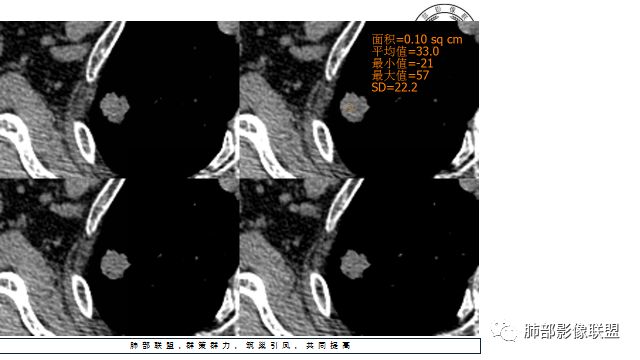

3.平扫病灶密度密度不甚均匀,外侧份见微小高密度影。

4.增强扫描成明显环形强化,中央液化坏死,内壁清楚且较为规整。